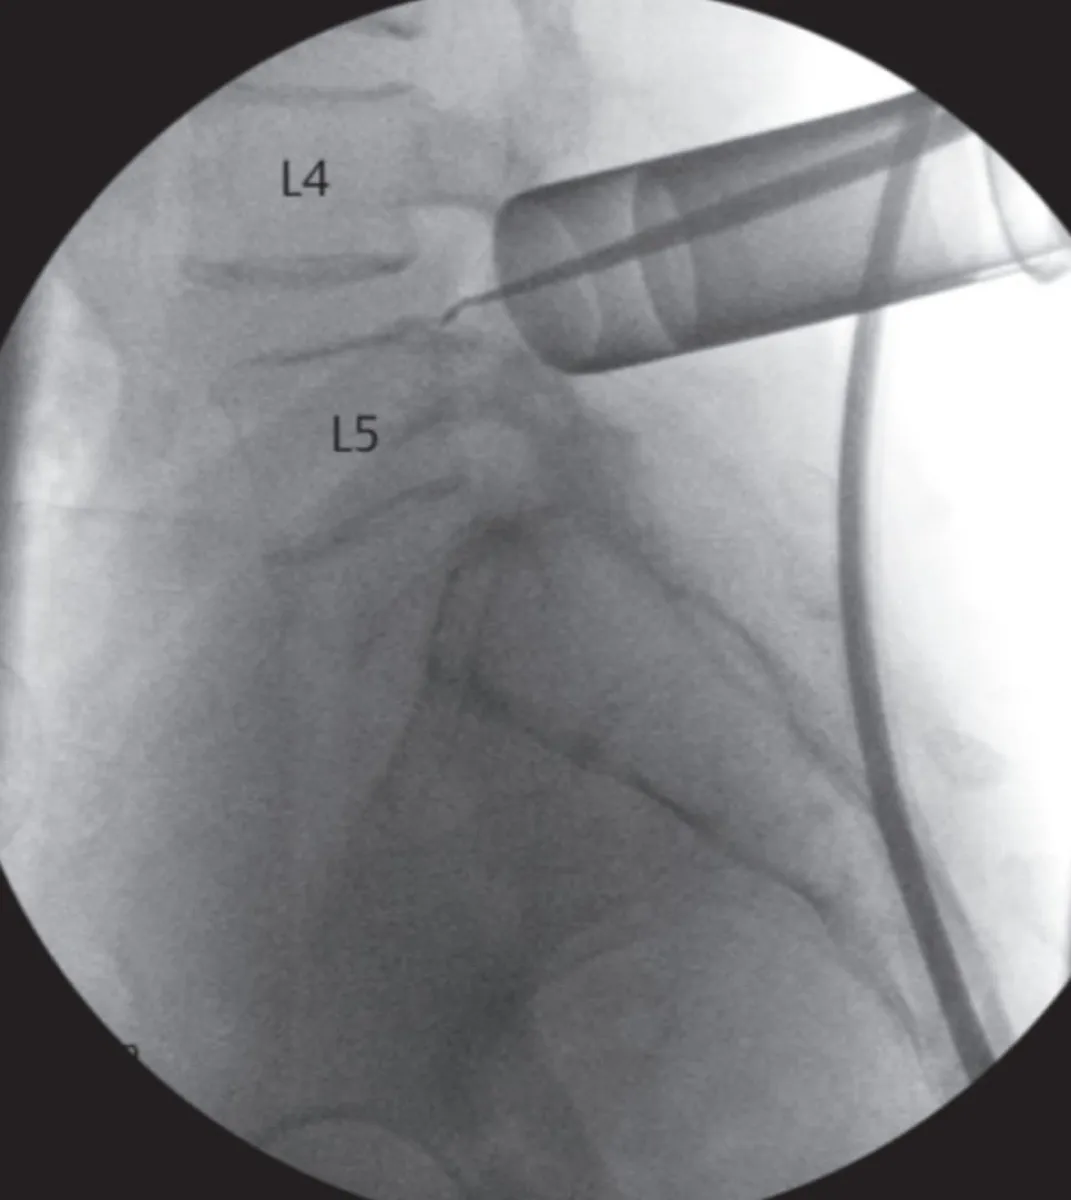

Se utilizan técnicas mínimamente invasivas (MISS, por sus siglas en inglés: Minimally Invasive Spine Surgery).

Desde salud remarcaron que se fueron incorporando prácticas quirúrgicas de alta complejidad y mínima invasión en el tratamiento de patologías de columna vertebral. Además de las técnicas quirúrgicas convencionales que siempre se realizaron en el hospital para el tratamiento de fracturas, tumores y enfermedades degenerativas, desde hace más de un año se han incorporado intervenciones mediante técnicas mínimamente invasivas (MISS, por sus siglas en inglés: Minimally Invasive Spine Surgery).

Estas técnicas, que se realizan a través de sistemas tubulares, representan un gran avance en el abordaje de patologías como hernias de disco, artrosis, compresiones medulares y radiculares, así como en el tratamiento de diferentes tipos de tumores, tanto benignos como malignos. Entre sus ventajas, se destacan la menor lesión de tejidos blandos, una reducción significativa del sangrado y del dolor postoperatorio, menor riesgo de infecciones y una recuperación más temprana.